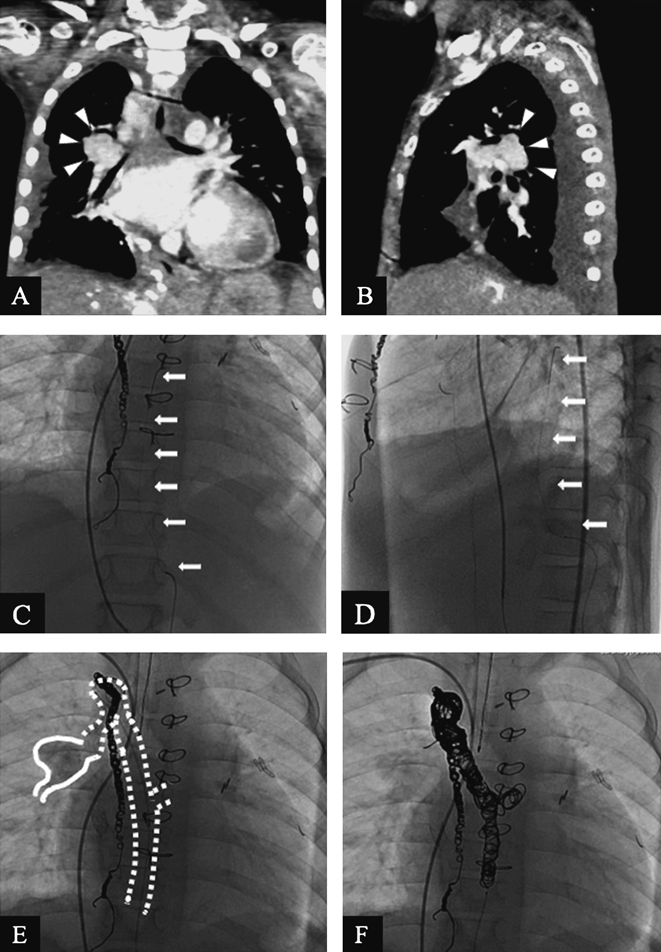

症例2:7歳,女児,静脈–静脈短絡

フォンタン循環不全の重症心不全患者で,不穏状態から重度低酸素血症をきたし,アシドーシスから徐脈となり集中治療を必要とした患者.フォンタン循環における静脈–静脈短絡に対する閉鎖術に関しては低酸素血症の改善は見込める可能性はあるものの,心拍出量低下と中心静脈圧上昇を来すため適応に関してより慎重に判定する必要がある.本来であれば閉鎖試験を行い,心拍出量と中心静脈圧の変化を確認して,閉塞を行うか否か決定することが望ましいが,本症例は多数の短絡のため閉鎖試験が極めて困難なことと,低酸素血症により著しい状態悪化を来したため,合同カンファレンスにて急性期を乗り切るために静脈–静脈短絡閉鎖術を行う方針となった.造影CTを示す(Fig. 2-A, B).多数の体静脈が集まり一塊となり右肺静脈へ還流する体静脈–肺静脈短絡を認めるが詳細な解剖はCTでは不明であった.両側大腿静脈および内頸静脈閉塞のため右腋窩静脈からのアプローチとしたが,右腋窩静脈から直接に右肺静脈に到達するルートは同定できず,いったん下大静脈までマイクロカテーテルを下ろして,標的血管を探し,左腎静脈から奇静脈を経由し右上肺静脈に還流する体静脈–肺静脈短絡を同定し,ガイドワイヤーを標的血管近くまで到達させることができた(Fig. 2-C).蛇行が強くマイクロカテーテルはセレクティブタイプしか到達させることができず,造影は不十分であったが,造影CTの画像を参考にコイル径を決定した.対象血管の違いはあっても基本的な留置手技としては症例1と変わらない.ただし,本症例ではマイクロカテーテルの屈曲点も多いため,コイルを送り出す際の手元に伝わる感触が伝わりにくいことを危惧し最初に留置するコイルはSR機構を有するもの,および肺静脈に突出しないような巻き方になるように何度も巻き直すことも考慮して再留置可能時間が20分と長いAzur CX 18コイルを留置し,その後は直前のコイルの巻き具合を確認しながら追加コイルを留置した.合計13本のコイルを用いて手技を終了した(Fig. 2-D).留置した全13本のコイルを留置順にTable 2に列記する.低酸素血症に関しては閉塞前後でSaO2 62%→85%と改善を認めた.対象血管へのアプローチに難渋し,蛇行も強いためマイクロカテーテルしか到達させることができず,コイルでなければ介入できなかった症例であった.

Fig. 2 Veno-venous collaterals: A) Coronal CT angiography shows veno-venous collaterals (arrowhead). B) Sagittal CT angiography shows veno-venous collaterals (arrowhead). C, D) The microcatheter (arrow) was advanced through 4 Fr catheter into the left renal vein to the azygos vein. C: antero–posterior view D: lateral view. E) The microcatheter was further advanced from the azygous vein (white dot) to the right upper pulmonary vein (white line). F) Coil (arrowhead) embolization for veno-venous collaterals was completed.

Table 2 Coil used in case 2

CoilDiameter-LengthNo of coil

Azur CX1820 mm–40 cm3

Azur CX1816 mm–39 cm2

Azur 1810 mm–20 cm1

Azur CX1812 mm–38 cm1

Azur CX188 mm–28 cm1

Azur 188 mm–20 cm1

Azur CX1810 mm–32 cm1

Azur 186 mm–10 cm2